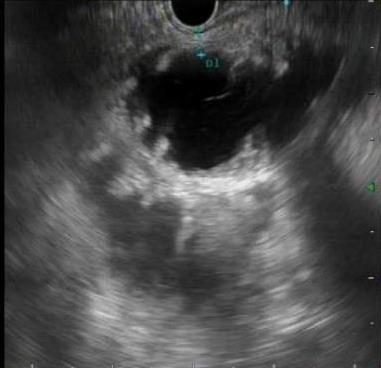

• 超声内镜引导下胃旁曲张静脉精准断流术治疗食管胃静脉曲张出血的疗效分析(附20例报告)

2025, 31(8):85-90. DOI: 10.12235/E20250036

摘要 (153) HTML (42) PDF 5.38 M (98) 评论 (0) 收藏

摘要:目的 探讨超声内镜引导下胃旁曲张静脉精准断流术治疗食管胃静脉曲张出血的疗效。方法 回顾性分析2024年1月1日-2024年12月31日于该院接受超声内镜引导下胃旁曲张静脉精准断流术治疗的20例肝硬化食管胃静脉曲张出血患者的临床资料,并评估治疗效果。结果 20例患者均顺利完成超声内镜引导下胃旁曲张静脉精准断流术;注射组织胶联合置入弹簧圈(16例)和单独注射组织胶(4例)均成功阻断胃旁来源的曲张静脉;所有患者均未发生穿孔、食管贲门狭窄、大出血、败血症和异位栓塞。1例单独注射组织胶的患者,术后胃旁曲张静脉少许渗血,经降低门静脉压力治疗3 d后好转,另1例单独注射组织胶患者,术后出现低热,抗感染3 d后体温恢复正常。结论 超声内镜引导下胃旁曲张静脉精准断流术治疗食管胃静脉曲张出血的临床疗效好,异位栓塞、大出血、感染和穿孔等并发症少,但仍需要密切随访,观察胃旁曲张静脉的排胶问题。